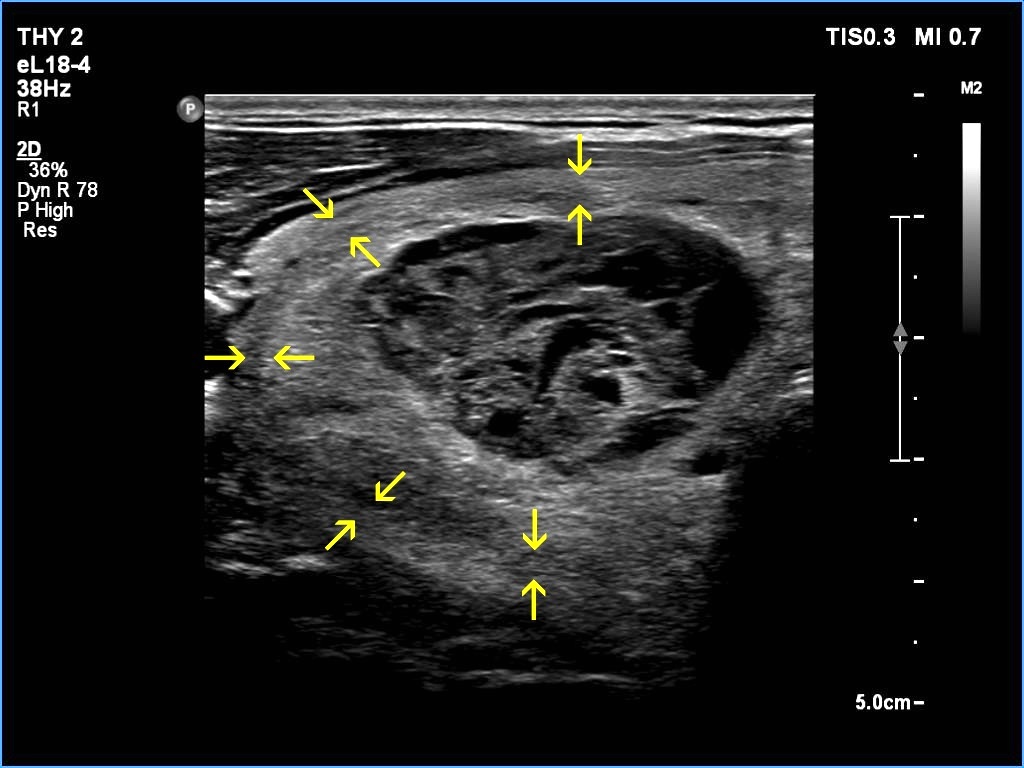

Right lobe, longitudinal scan

Right lobe, transverse scan. The arrow pairs point to the border of the nodule.